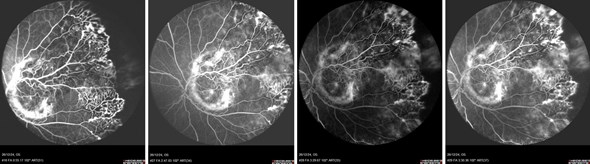

Participants were asked to select the most likely diagnosis. Despite calcification, further investigations including fluorescein angiography (Figures 3a-d) and optical coherence tomography (OCT) supported a diagnosis of Coats disease, and the child was managed conservatively with peripheral cryotherapy and laser photocoagulation.

Figures 3a–d: Fundus fluorescein angiography highlighting vasculopathy with area of peripheral avascular zone.